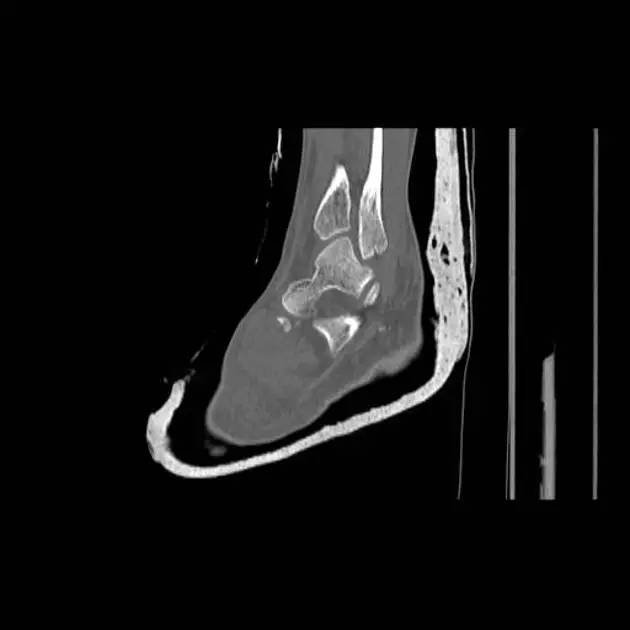

6. Pilon 骨折

涉及负重关节面(胫距关节面)与胫骨远侧干骺端的骨折。其典型特征是干骺端存在不同程度的压缩、干骺端的压缩粉碎性骨折不稳定、原发性关节软骨损伤以及永久性关节面不平整导致预后不良。

pilon 骨折正位片

pilon 骨折侧位片

pilon 骨折三维 CT 表现